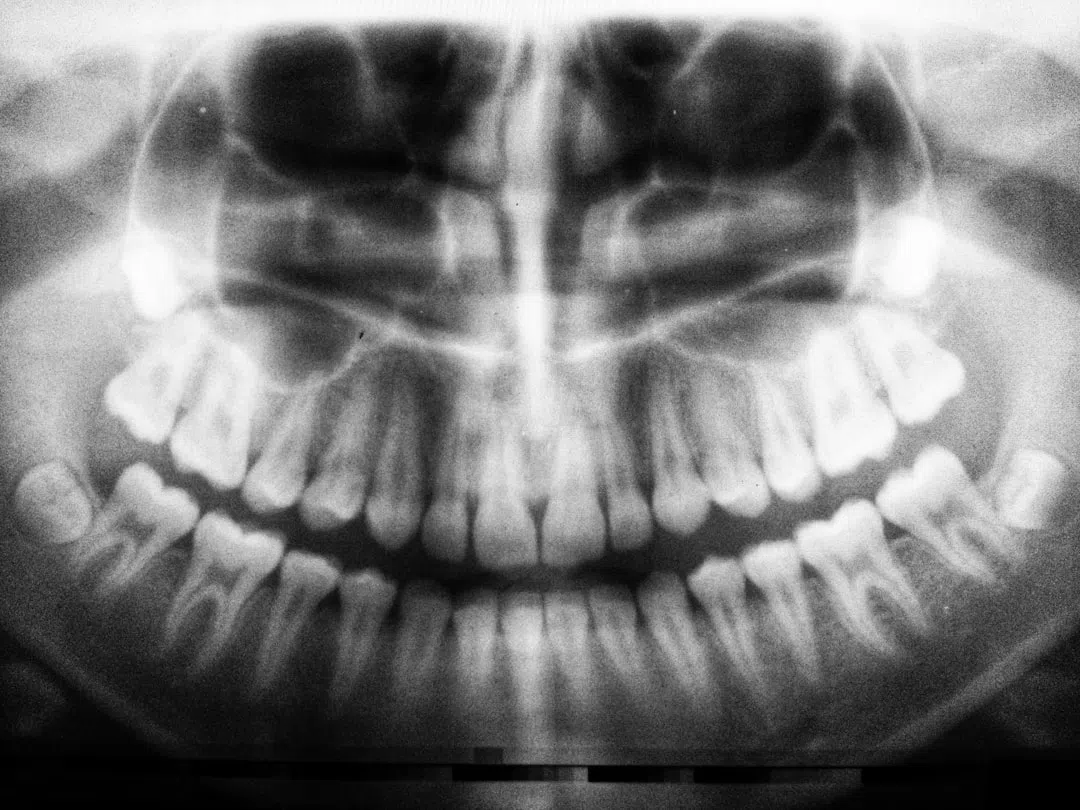

임플란트를 심기 전에 환자의 구강 상태를 평가하고, 필요한 경우 기존의 손상된 치아를 제거합니다. 사진 속 첫 번째 상태가 바로 임플란트 식립 전의 구강 상태입니다. 환자는 주로 전통적인 틀니를 사용하고 있으며, 이러한 상태에서 임플란트를 식립하게 됩니다.

다음으로 4개의 임플란트를 잇몸에 식립합니다. 임플란트는 잇몸의 앞쪽에 집중적으로 식립되는데, 이는 뒤쪽의 뼈가 약하거나 부족한 경우가 많기 때문입니다. 잇몸의 상태에 따라 임플란트의 개수와 위치가 결정되며, 사진에서는 위쪽에 4개의 임플란트가 식립된 모습을 볼 수 있습니다.

첫 번째 환자는 임플란트를 총 4개 식립하여 임플란트 틀니를 착용하게 되었습니다. 사진을 통해 임플란트가 어떻게 식립되었는지 확인할 수 있는데, 위쪽에 4개의 임플란트를 식립하고 이를 통해 틀니를 고정한 상태입니다. 임플란트가 틀니를 지지해 주어 기존의 틀니 사용에서 발생했던 불편함이 크게 줄어들었습니다.

두 번째 환자의 경우, 임플란트를 조금 더 적은 수로 식립하였습니다. 위쪽에는 3개, 아래쪽에는 2개의 임플란트를 심어 틀니를 고정하였는데, 이는 환자의 잇몸 상태와 뼈의 상태에 따라 결정된 것입니다. 특히, 뒤쪽의 뼈가 부족한 경우에는 앞쪽에만 임플란트를 식립하는 방식이 자주 사용됩니다. 이처럼 임플란트 식립은 환자의 상태에 따라 맞춤형으로 진행되며, 최소한의 임플란트로도 충분한 효과를 볼 수 있습니다.